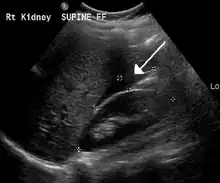

Small fluid collection in Morison's pouch

The use of ultrasound has become the standard of care when preparing a patient for paracentesis. Confirmation of an ascitic effusion reduces the risks associated with a dry or blind tap of the abdomen. Anatomic landmarks, such as the midline linea alba approach, were traditionally used as reference points for needle insertion. Phased array or curvilinear ultrasound transducers are typically used in the hospital and outpatient setting to identify ascites in the abdominal cavity. Fluid within the abdominal cavity appears hypoechoic or anechoic (black) on ultrasound. Morison's pouch (hepatorenal recess) is a common starting location in concordance with ultrasound FAST (focused assessment with sonography for trauma) exam. Fluid collection can occur in a number of different locations and may be difficult to find, especially if the patient only exhibits a small volume of ascites. Measurement of the amount of fluid within the abdominal cavity is not necessary or very successful. Identification of sufficient fluid within the abdominal cavity for fluid analysis or to achieve a therapeutic benefit is all that is required to proceed to paracentesis. Ultrasound guidance of the paracentesis can also be used as an additional safety measure to ensure the needle stays within the ascitic fluid and avoidance of important vessels within the abdominal cavity. [5]